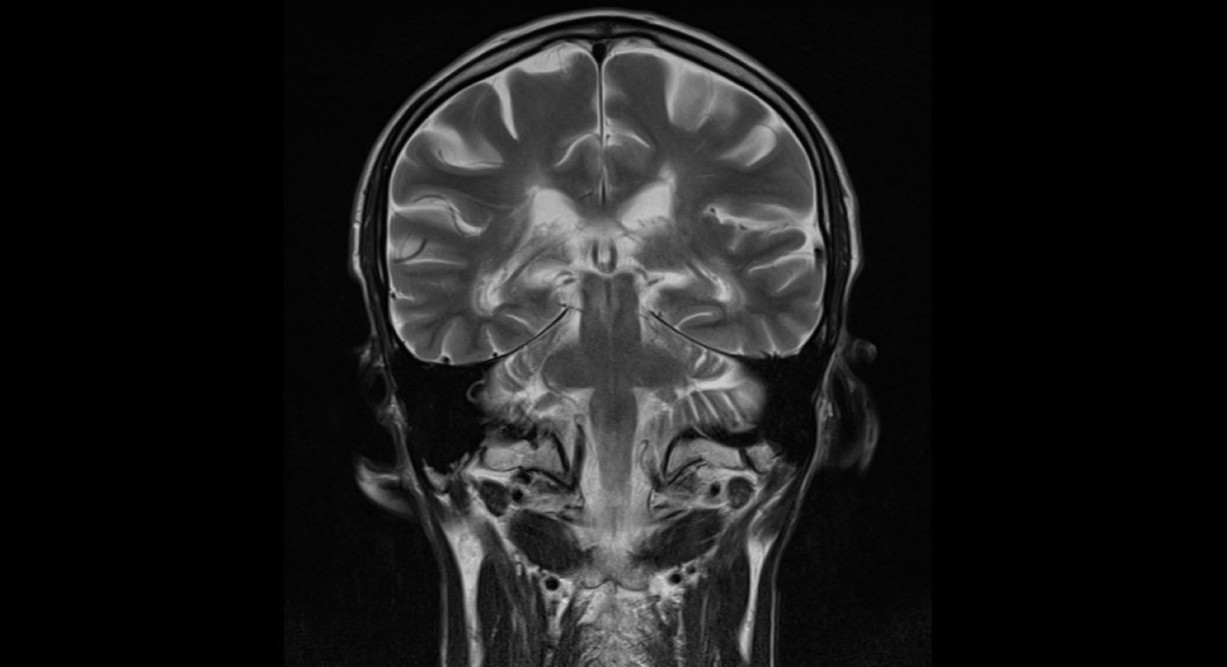

В октябре 2025 года были опубликованы новые диагностические критерии рассеянного склероза, в которых важнейшую роль играет магнитно-резонансная томография головного и спинного мозга. Предстоящая научно-практическая конференция организована с целью актуализации знаний и улучшения качества оказания медицинской помощи. Ведущий лектор на конференции - научный сотрудник Российского центра неврологии и нейронаук Василий Валерьевич Брюхов. Это мероприятие будет интересно в первую очередь для врачей радиологов, неврологов и нейрохирургов.

16:05 - 16:35 доклад «Новое в МРТ критериях для диагностики рассеянного склероза» - Брюхова Василия Валерьевича, к.м.н., старшего научного сотрудника ФГБНУ «Российский центр неврологии и нейронаук».